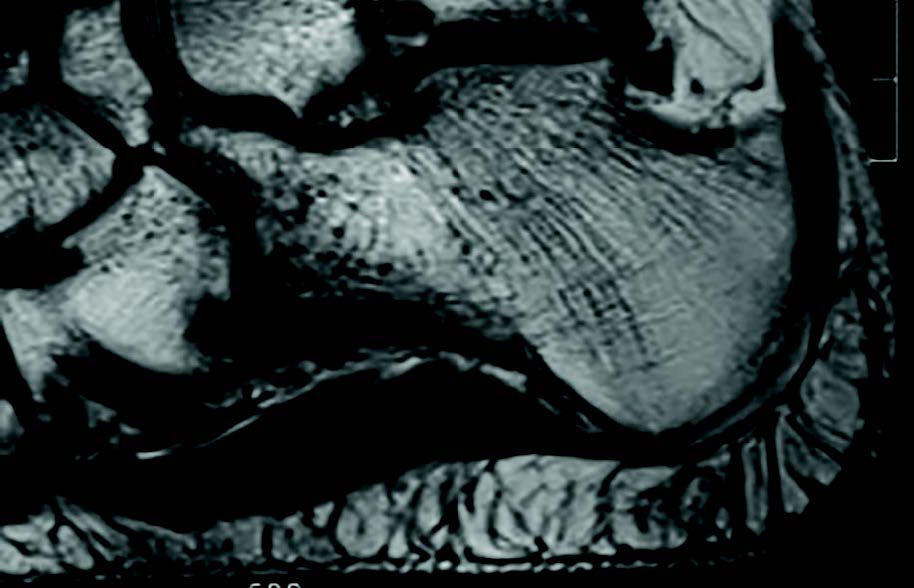

The plantar fat pad does not help in either case. The elliptical adipocytes, perpendicular to the weightbearing surface of the heel and tightly constrained by fibrous septae, are largely avascular (see second image above). This enhances failure in two ways. First, the fibrous channels permit longitudinal bacterial communication. Transmission from deep to superficial tissue planes and vice versa allows rapid tissue degradation, resulting in full-thickness liquefaction. Second, as local trauma rages, the tightly loculated adipocytes swell. In a cascade of cytokines and interleukins, perfusion to this already avascular structure slows.7 Eventual edema stymies local perfusion pressure and a microscale compartment syndrome ensues. Gross necrosis and tissue loss prevail.